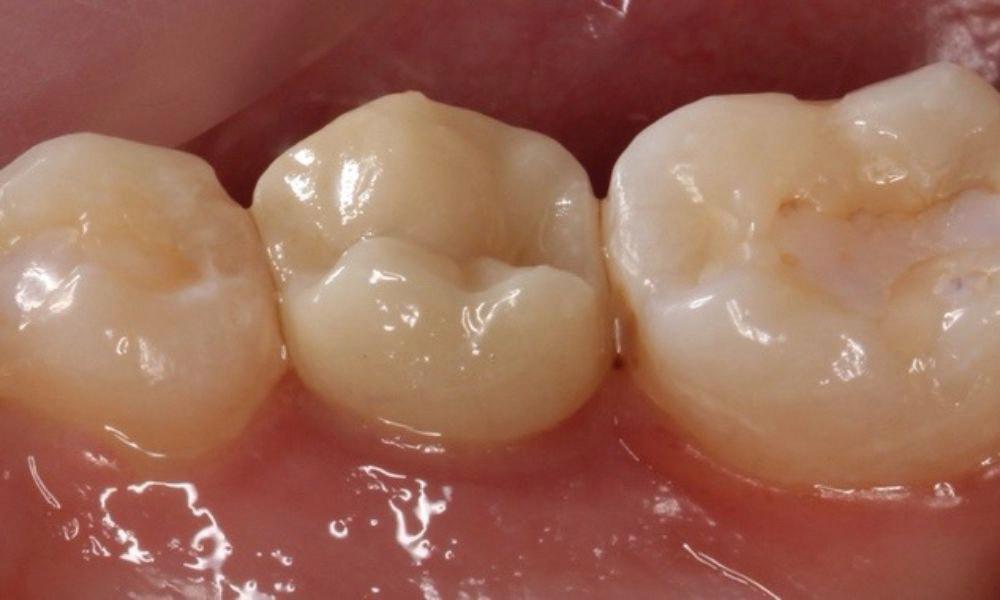

Estelite Asteria (Tokuyama)One of my favourite composite resin materials is Asteria which is a light-cured radiopaque composite for universal use. It considerably simplifies multilayer techniques yet delivers outstanding aesthetics with excellent polishability. Unlike mul tilayer techniques used with conventional composites, Asteria uses only 2 layers for optimal results without compromising aesthetics. The microstructure of the material produces a light diffusion that helps blend in with the natural tooth structure. The chameleon like nature of the material allows a blending of the materials to natural tooth structure and it allows excellent polishability which retains its lustre over time.